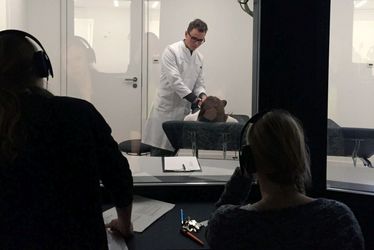

9. Small Animal Imaging Workshop - The Mouse Imaging Academy (MIA) Münster

9. Small Animal Imaging Workshop - The Mouse Imaging Academy (MIA) Münster

9. Small Animal Imaging Workshop - The Mouse Imaging Academy (MIA) Münster

9. Small Animal Imaging Workshop - The Mouse Imaging Academy (MIA) Münster